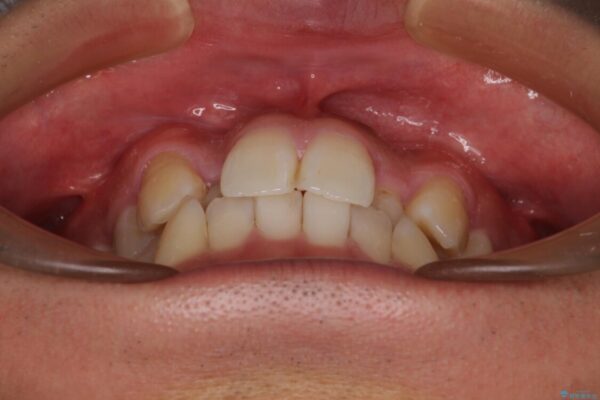

「八重歯を治したい」とご相談いただいた患者様の症例をご紹介します。

上下の前歯部に強い叢生(ガタガタの歯並び)があり、そのまま歯を並べると出っ歯になってしまう可能性がありました。

治療前

• 八重歯と前歯のガタガタを抜歯矯正で治療|クリアブラケット使用例 治療前画像